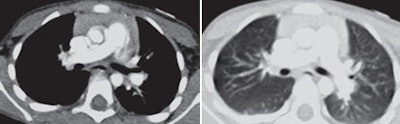

| Above images show a 3-year-old boy weighing 14.7 kg (32.3 lb) imaged with 120 kVp and measured noise of 9.6 HU. Images below are of a 4-year-old boy weighing 14.1 kg (31 lb) imaged with 80 kVp and measured noise of 11.3 HU. All transverse CT images with mediastinal and lung windows were rated as having good image quality. Images courtesy of the American Journal of Roentgenology. |